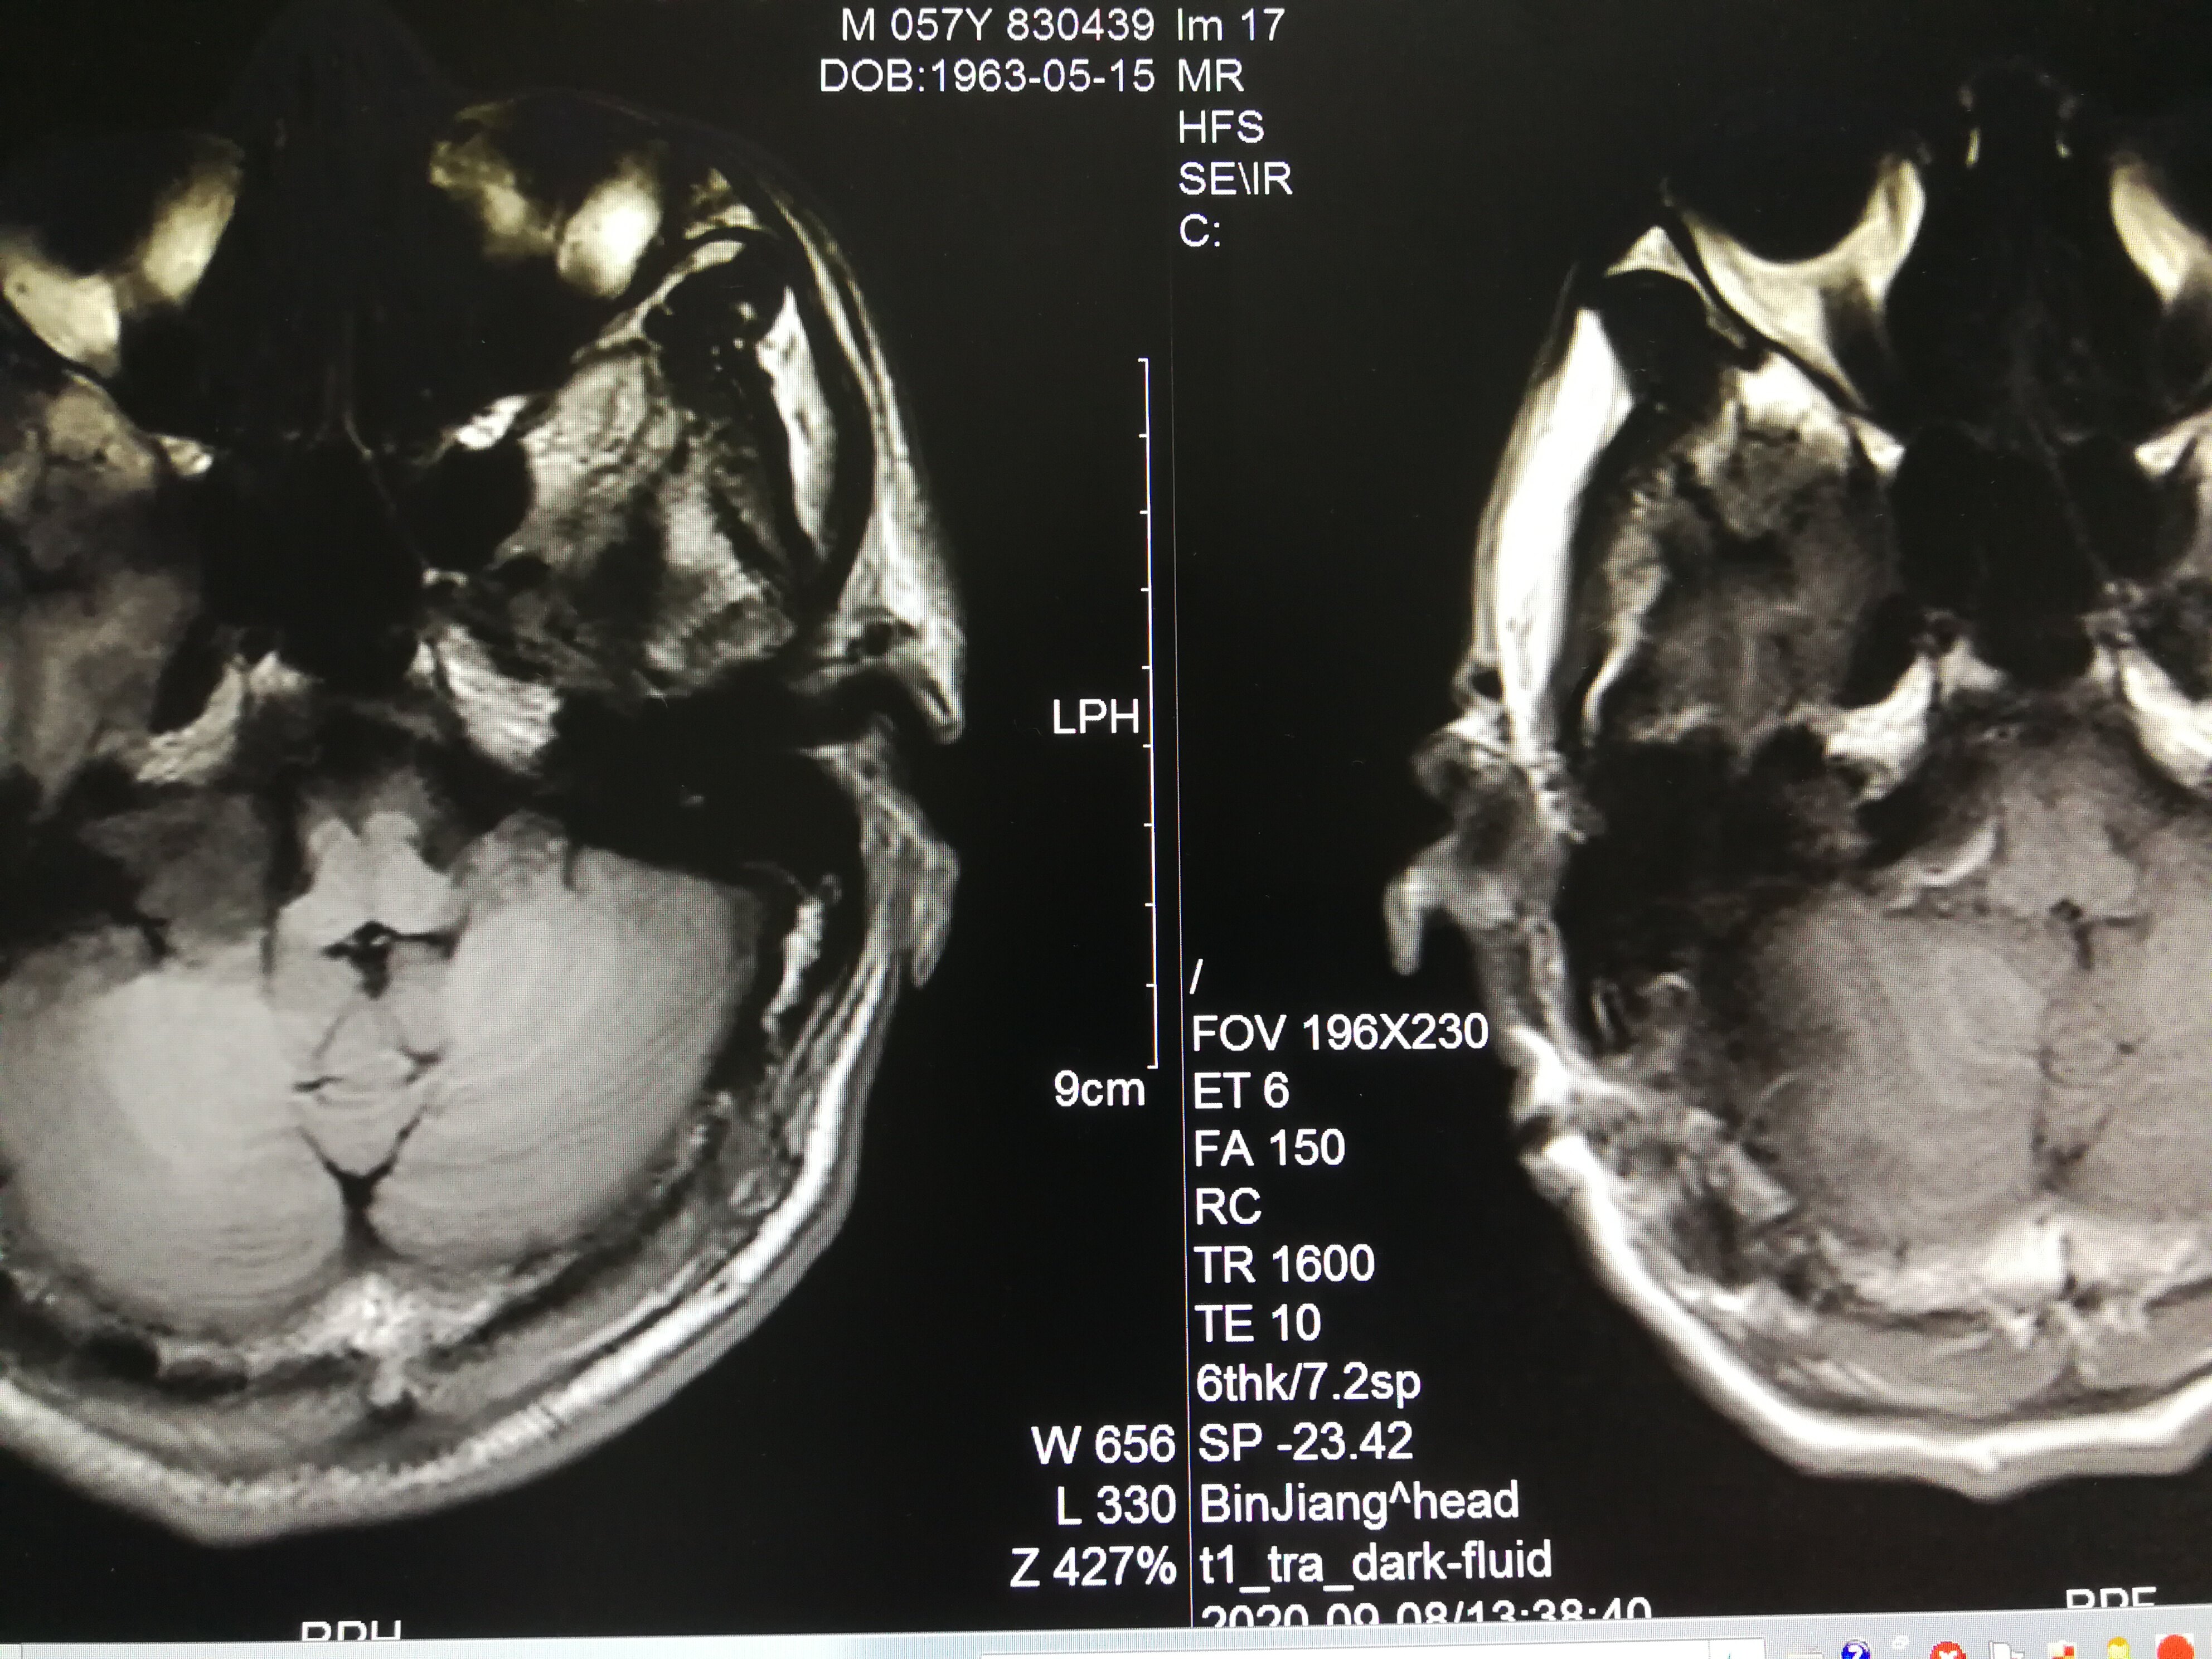

手术治疗听神经瘤是最主要的治疗方式,目前听神经瘤的手术已经非常成熟,只要没有明显的手术禁忌症首先应考虑手术治疗,并要求在电生理监测条件下完成手术,这样可以最大限度地保护面神经功能。以下是几例我们做的听神经鞘瘤手术前后核磁共振片子对照,除手术后听力不能恢复外,没有面瘫,脸部麻木,吞咽困难等颅神经症状,也无其他较明显的手术并发症发生。